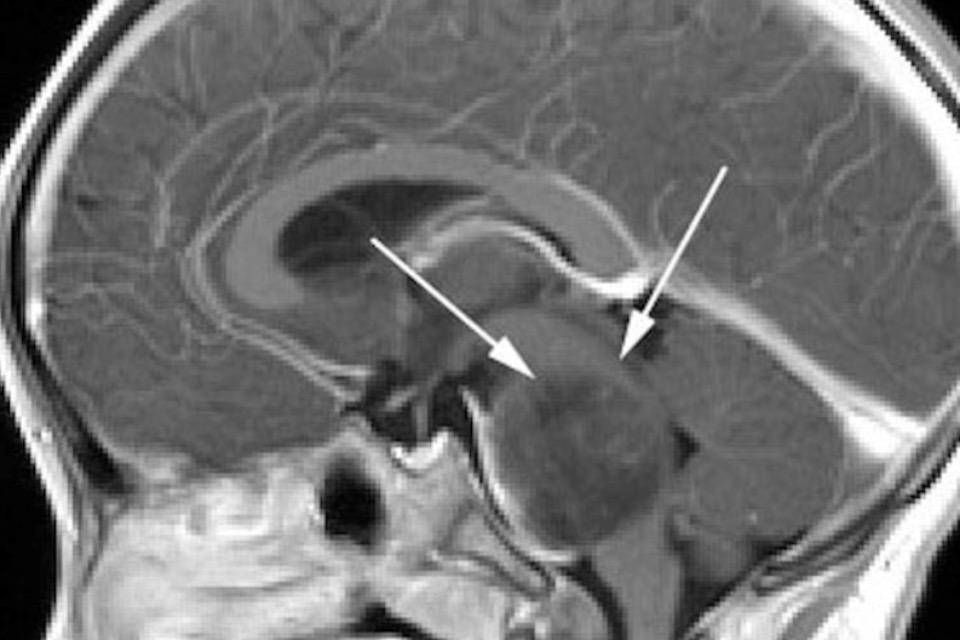

この病気は、脳の中枢にある脳幹部の内部に悪性腫瘍(がん)が発生する病気で、病名の告知と同時に約1年の余命を宣告されるという小児がんの中でも最も厳しい疾患の一つです。

生命活動を維持するためのあらゆる神経がびっしりと通っている脳幹内部の腫瘍を、神経を傷つけずに外科的に摘出するのは、どんな神の手の脳外科医でも不可能です。また、あらゆる抗がん剤が効きません。唯一の治療は放射線治療で、一時的に腫瘍の縮小と、症状の緩和期が訪れますが、約半年以内に再び腫瘍が増大し、その後は、医学的に確立された治療法はありません。